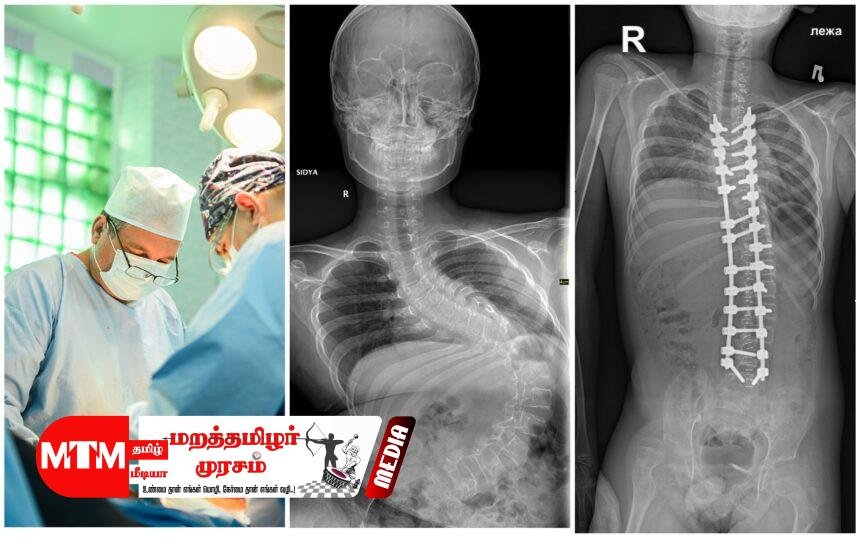

கடந்த சில மாதங்களாகவே புத்தளம் தள வைத்தியசாலையில் பல்வேறு முள்ளந்தண்டு சத்திரசிகிச்சைகள் முன்னெடுக்கப்பட்டு வந்த போதிலும், முள்ளந்தண்டு வளைவைச் சீர்செய்யும் இந்த ‘Scoliosis Correction’ சிகிச்சை அங்கு இடம்பெற்றது இதுவே முதல் முறையாகும். பொதுவாக இச்சிகிச்சையானது கொழும்பு, கண்டி, யாழ்ப்பாணம், பதுளை மற்றும் இரத்தினபுரி போன்ற பிரதான போதனா வைத்தியசாலைகளில் மட்டுமே வழங்கப்பட்டு வந்தது. என்பு முறிவு விசேட வைத்திய நிபுணர் டாக்டர் ஷெஸார் ஹமீத் தலைமையில் இந்த அறுவை சிகிச்சை நடைபெற்றது. இவருடன் தேசிய வைத்தியசாலையின் சிரேஷ்ட என்பு முறிவு விசேட வைத்திய நிபுணர் டாக்டர் உதை டி சில்வா,

லேடி ரிஜ்வே வைத்தியசாலையின் விசேட வைத்திய நிபுணர் டாக்டர் நிர்மல் மாரசிங்ஹ, நினைவிழக்கச் செய்யும் விசேட வைத்தியர் (Anesthetist) டாக்டர் சரிந்த ஆகியோர் அடங்கிய மருத்துவக் குழுவினர் இப்பணியை செவ்வனே நிறைவேற்றினர்.